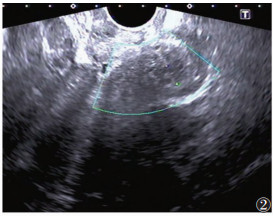

超声共发现病灶区101个(图 1~4),敏感度79.5%,超声诊断与手术结果对照见表 1。经阴道超声诊断的最低敏感度(64.4%)和准确率(79.7%)在阴道,最高敏感度(94.6%)和准确率(97.5%)在直肠子宫陷凹。

| 图 2 42岁,宫颈病灶,主诉性交疼痛,超声示宫颈后唇低回声区,边界不清,内见细小无回声区,血流信号不明显,触痛明显 |

DIE病灶超声表现:呈结节状、片状或不规则形,边界欠清、不规整。可与周边组织粘连;多为低回声区,偶为等、高回声区,内部回声不均匀,可见细小无回声区,透声欠佳,CDFI可见部分病灶散在短杆或点状的穿枝型血流病灶(17/101,16.8%)。

各部位DIE病灶的诊断要点:①宫骶韧带表现为宫颈下段两侧旁结节样或条索样低不规则回声区;宫旁组织、子宫浆膜面病灶呈不规则片状或斑块状低回声,注意与子宫浆膜下肌瘤鉴别。②超声直接在输尿管周围或内部发现明显病灶较困难,伴输尿管扩张的DIE可增加诊断率,本研究中2例均因输尿管扩张而诊断,但需注意排除,如结石、先天性狭窄等梗阻因素。③膀胱病灶由于尿液透声窗衬托,诊断敏感度较高,病灶常见于后壁,呈低回声结节,可局限于膀胱浆膜面,超声可评估病变的侵犯深度。④本研究中经阴道超声对直肠子宫陷凹病灶诊断敏感度和准确率最高,与文献[8]报道一致,直肠子宫陷凹粘连封闭为DIE显著特征,也可表现为不规则低回声区,与子宫后壁分界不清。⑤阴道、直肠、阴道直肠隔DIE病灶常经妇检首先发现,经阴道超声诊断敏感度偏低,表现为局部不规则低回声区,探头触痛,检查中注意分清三者毗邻结构关系,精确定位病灶侵犯部位。直肠病灶常与宫颈后区病变粘连,造成直肠子宫陷凹闭锁。⑥DIE超声表现虽有一定的特征性,但也需与盆腔脏器恶性肿瘤鉴别。DIE病灶对腹膜脏器浸润是从外(浆膜层)向内(肌层),而肿瘤对肠壁脏器的浸润则是自内(黏膜层)向外(浆膜层)。直肠子宫陷凹病灶需与肿瘤的腹膜转移灶鉴别,两者表现相似,但肿瘤结节的外形较规则,CDFI血流信号丰富,而DIE形态多呈不规则斑片状,CDFI血流信号稀少;且转移瘤常伴腹腔积液,结合其他辅助检查可发现相关原发肿瘤,有助于确诊。

各部位DIE病灶的诊断要点:①宫骶韧带表现为宫颈下段两侧旁结节样或条索样低不规则回声区;宫旁组织、子宫浆膜面病灶呈不规则片状或斑块状低回声,注意与子宫浆膜下肌瘤鉴别。②超声直接在输尿管周围或内部发现明显病灶较困难,伴输尿管扩张的DIE可增加诊断率,本研究中2例均因输尿管扩张而诊断,但需注意排除,如结石、先天性狭窄等梗阻因素。③膀胱病灶由于尿液透声窗衬托,诊断敏感度较高,病灶常见于后壁,呈低回声结节,可局限于膀胱浆膜面,超声可评估病变的侵犯深度。④本研究中经阴道超声对直肠子宫陷凹病灶诊断敏感度和准确率最高,与文献[8]报道一致,直肠子宫陷凹粘连封闭为DIE显著特征,也可表现为不规则低回声区,与子宫后壁分界不清。⑤阴道、直肠、阴道直肠隔DIE病灶常经妇检首先发现,经阴道超声诊断敏感度偏低,表现为局部不规则低回声区,探头触痛,检查中注意分清三者毗邻结构关系,精确定位病灶侵犯部位。直肠病灶常与宫颈后区病变粘连,造成直肠子宫陷凹闭锁。⑥DIE超声表现虽有一定的特征性,但也需与盆腔脏器恶性肿瘤鉴别。DIE病灶对腹膜脏器浸润是从外(浆膜层)向内(肌层),而肿瘤对肠壁脏器的浸润则是自内(黏膜层)向外(浆膜层)。直肠子宫陷凹病灶需与肿瘤的腹膜转移灶鉴别,两者表现相似,但肿瘤结节的外形较规则,CDFI血流信号丰富,而DIE形态多呈不规则斑片状,CDFI血流信号稀少;且转移瘤常伴腹腔积液,结合其他辅助检查可发现相关原发肿瘤,有助于确诊。